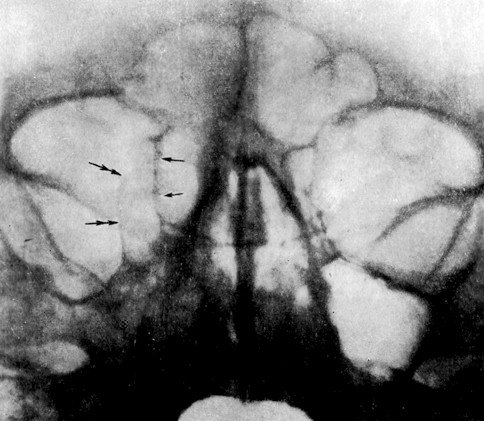

Мукоцеле правого решетчатого лабиринта

Мукоцеле (слизистая киста) представляет собой безболезненный, тонкостенный пузырь придаточных полостей носа, на внутренней поверхности губ. Содержит прозрачную жидкость.